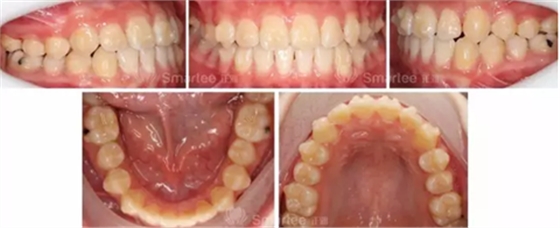

(矯治12個月,第一次精調(diào))

(矯治14個月,第一次精調(diào)2個月)

(矯治前后反饋情況對比)

1)隱形矯治器配合牙合墊附件,對于前牙反牙合的解除起到了重要作用。

2)通過優(yōu)化附件的使用,很好的整平了spee曲線。

3)通過增加控根附件,11、21做到了良好的控根移動。